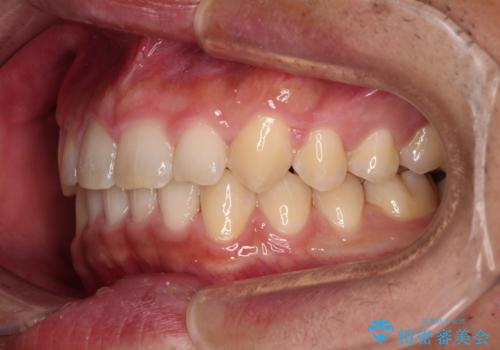

- 前歯の隙間と深い咬み合わせを改善したいとのことで来院された患者様です。

マウスピース矯正の自己管理が面倒とのことで、ワイヤー矯正により治療を行うこととしました。

奥歯の咬み合わせは理想的な状態であったため、ワイヤー矯正でもインビザラインでも比較的容易に対応可能でした。